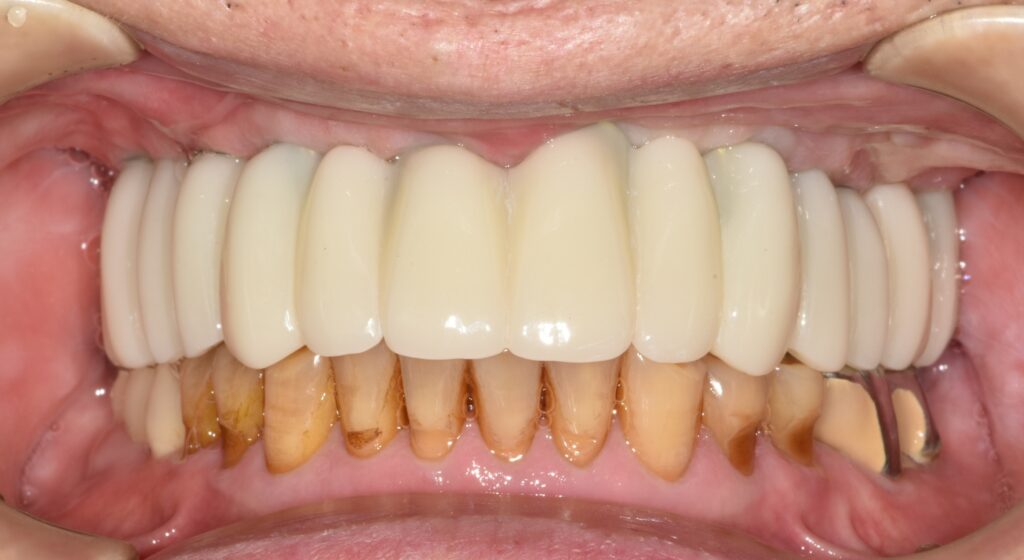

최종 보철 장착

충분한 적응 기간을 거친 후, 문제가 없음을 확인하고 최종 보철을 제작 및 장착하였습니다.

이 단계에서는 단순히 치아를 넣는 것이 아니라 기능과 안정성까지 고려한 정밀한 마무리 과정이 이루어집니다.